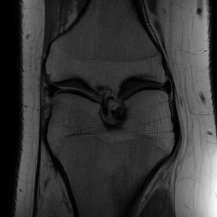

| Ground Truth | Initial | Global | LONDN-MRI | LONDN-MRI | Oracle |

| (1 iteration) | (2 iterations) | ||||

![]() |

| PSNR = dB | PSNR = 22.01 dB | PSNR = 29.02 dB | PSNR = 31.46 dB | PSNR = 31.74 dB | PSNR = 31.87 dB |